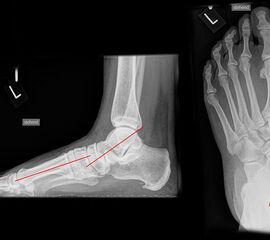

Röntgenaufnahmen des Fußes d.p., streng seitlich und schräg unter Belastung. Saltzmann Aufnahme zur Beurteilung der Rückfussachse.

Operationsplanung anhand der Röntgenaufnahmen unter Beachtung wichtiger radiologischer Landmarks wie Rückfussachse, Metatarsale I – Talushals-Achse im dp und lateralen Strahlengang (Abbildung 1 und 2).

Abbildung 2